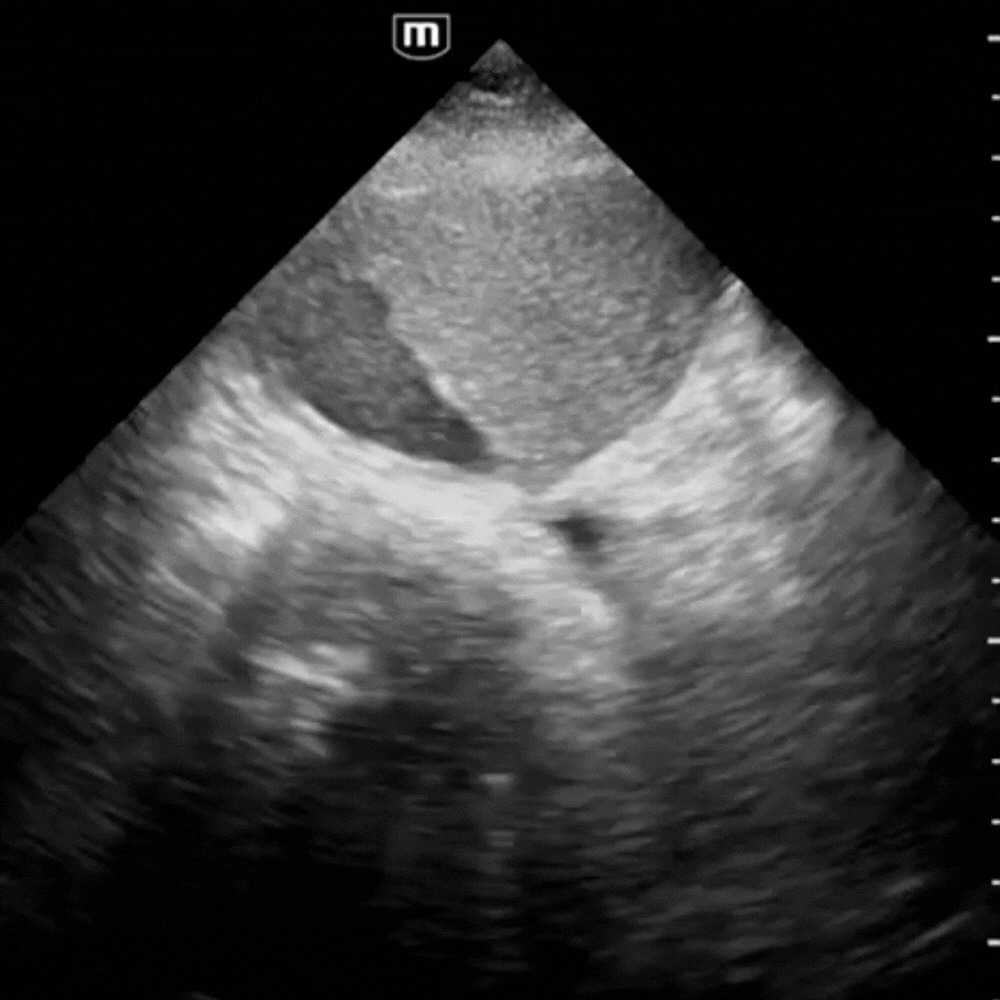

⚠️ Signes de Pathologie

- Anévrysme fusiforme ou sacculaire : dilatation > 3 cm, souvent avec calcifications pariétales.

- Thrombus mural : zone échogène pariétale sans flux au Doppler.

- Rupture : hématome rétro-péritonéal hétérogène, parfois difficile à distinguer ; rechercher un épanchement libre.

🚨 Un AAA > 5,5 cm ou douloureux = urgence chirurgicale absolue.